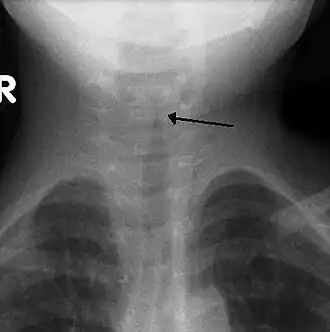

![]() Симптом «остро заточенного карандаша» на рентгенограмме гортани в прямой проекции | |

Может быть информативна рентгенография гортани. У детей с крупом при рентгенографии в боковой проекции может визуализироваться отёк гортаноглотки с сужением подскладочного пространства гортани (в прямой проекции имеющим вид классического симптома «остро заточенного карандаша»)[5].